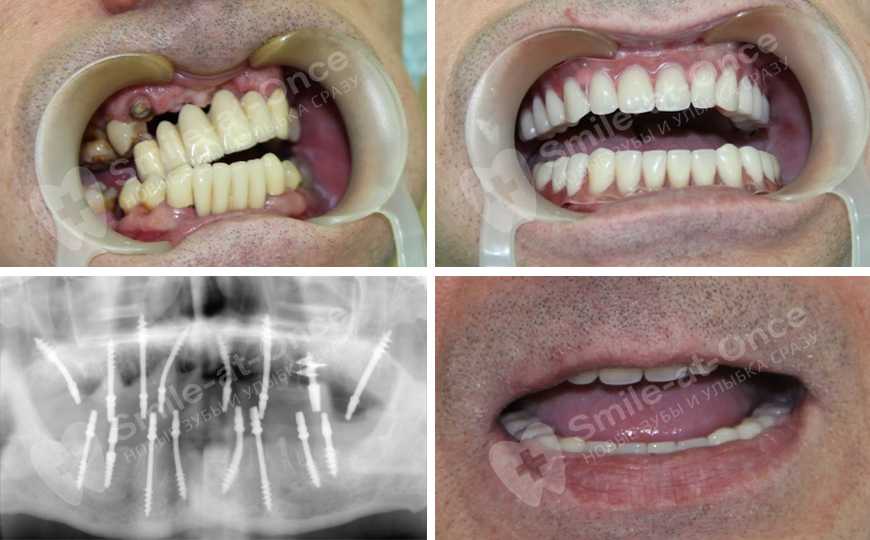

— А что касается протеза – насколько он функционален и можно ли добиться его эстетики?

— При моментальной нагрузке можно добиться самой высокой эстетики – и в этом одна из наших основных задач: чтобы пациент после лечения не только полноценно питался, но и наслаждался собственным отражением в зеркале. На имплантах фиксируется несъемный протез, жевать им мягкую пищу можно сразу, постепенно нагрузку необходимо увеличивать – в среднем через месяц пациент полностью возвращается к привычной жизни. Протез состоит из коронок и имеет небольшую часть искусственной акриловой десны – она нисколько не нарушает внешний вид протезов. А, напротив, позволяет скрыть недостатки натуральной слизистой – ее неровный контур, который образуется при проседании костной ткани и воспалении пародонта. Такой протез необходимо носить минимум полгода-год, до полного приживления имплантов в кости. Впрочем, на практике мы видим, что такие протезы вполне успешно служат 3-5 лет.